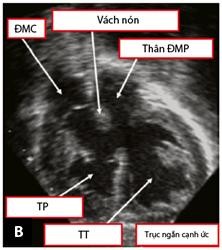

Tiếp theo đó, mặt cắt cạnh ức cao trên trục ngắn cho phép đánh giá tương quan giữa hai đại động mạch và mối liên quan của chúng với lỗ TLT, đánh giá tình trạng của đường ra của các tâm thất (Hình 1.13). Mặt cắt này còn giúp đánh giá xuất phát và đường đi của hai ĐMV. Mặt cắt cạnh ức thấp trên trục ngắn cho phép khảo sát tình trạng của thân và hai nhánh của ĐMP [59],[83].

Hình 1.13: Mặt cắt cạnh ức trong chẩn đoán TPHĐR. (A) Hình ảnh TPHĐR thể chuyển gốc qua mặt cắt cạnh ức trục dài. (B) Mặt cắt cạnh ức trục ngắn cho hình ảnh TPHĐR thể chuyển gốc với ĐMP cưỡi ngựa lên VLT 50% [53]